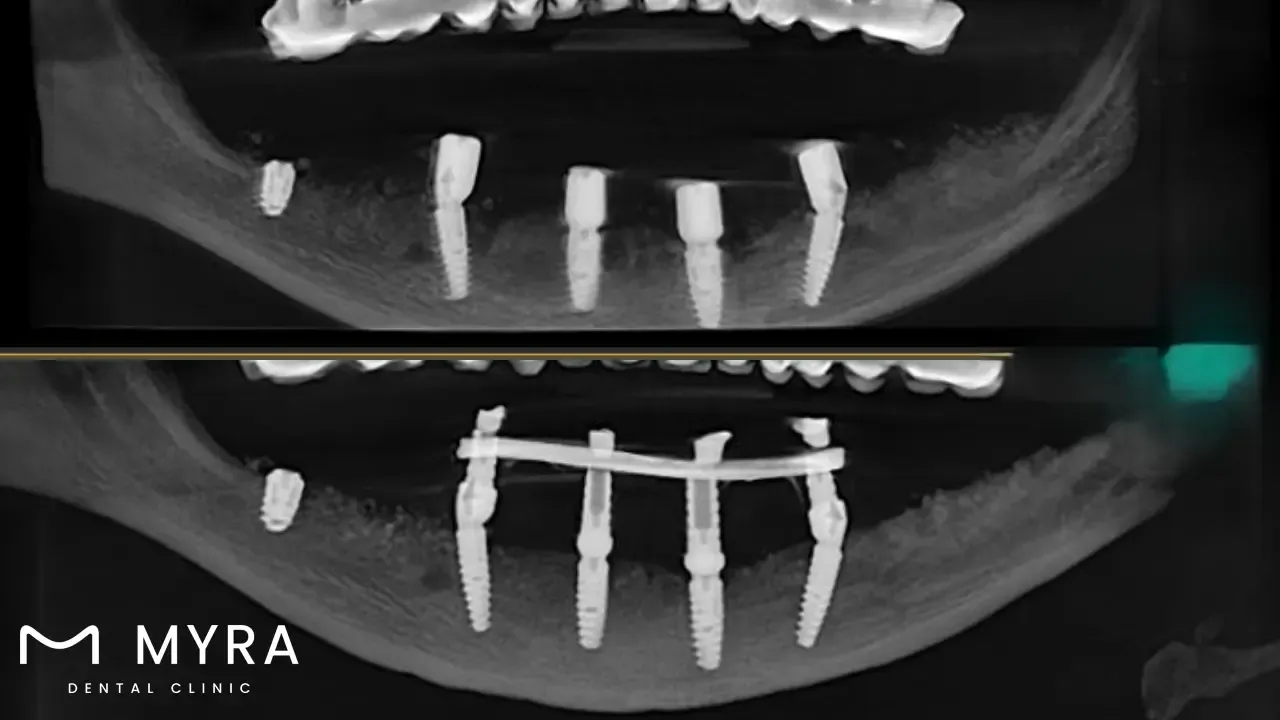

Titanium implants are common ways of restoring lost teeth. Titanium Implants are made up of a titanium post that is surgically placed into the jawbone to replace the missing tooth's root. Titanium is selected for its biocompatibility, strength, and longevity, making it an excellent choice for dental implants. The titanium post undergoes osseointegration, which merges with the surrounding bone to form a stable and permanent foundation for the dental prosthetic, such as a crown, bridge, or denture. The primary benefits of titanium dental implants are their strength and ability to maintain jawbone health. They stimulate bone and prevent bone loss by replicating the natural tooth root, which helps keep the face's structure and look.

A Titanium tooth implant offers a stable and solid anchor for dental restorations, allowing for proper biting and chewing capabilities. They have a high success rate and last a lifetime when maintained and upkeep. Installing “titanium teeth” implants consists of multiple stages, including initial evaluation, surgical implant insertion, a healing time for osseointegration, and the last attachment of the dental prosthesis. The treatment and healing take up to six months, resulting in a natural-looking and functioning tooth replacement that significantly improves longevity. The cost depends on the number of lost teeth, the dental clinic’s area, the complexity of the patient’s case, and the extra work needed.

Titanium is a critical component in dental implants, serving as the fundamental element of the implant root. The titanium part of a dental implant is a thin screw-like post that is surgically placed into the jawbone to replace a missing tooth's root. Titanium's inherent features, including biocompatibility, strength, and corrosion resistance, ensure that the implant endures the daily stresses of chewing and biting, providing a long-term solution for tooth replacement.

Place the implant. The dental implantation process takes place with local anaesthesia. The oral surgeon or implantologist makes an incision in the gum tissue to expose the jawbone before drilling a small hole for the titanium implant. The implant is gently inserted into the bone, like “teeth screws” in the gum, and the gum tissue is sutured together around it.

Do the Osseointegration. The dental process occurs after implantation when the implant bonds with the surrounding bone tissue. The procedure takes more months, during which the patient wears a temporary restoration to maintain aesthetics and function.

Put in the abutment. The implant requires a second surgical procedure to be attached to the bone after osseointegration is complete. The abutment connects the implant to the dental restoration.